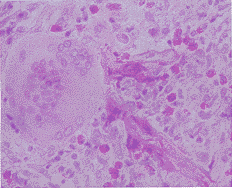

皮膚毛霉病凍土毛霉所致的原發性皮膚毛霉病皮

損組織病理學檢查(HE染色)

毛霉病的發病主要表現為鼻腦部、肺部、胃腸部、皮膚及全身播散感染5種形式。原發性皮膚毛霉病是最少見的形式,僅占報導病例的10%以下[4]。對於該病的診斷主要靠皮損組織活檢和組織病理檢查,直接鏡檢可見一些寬的、無間隔的、成直角分支的菌絲。